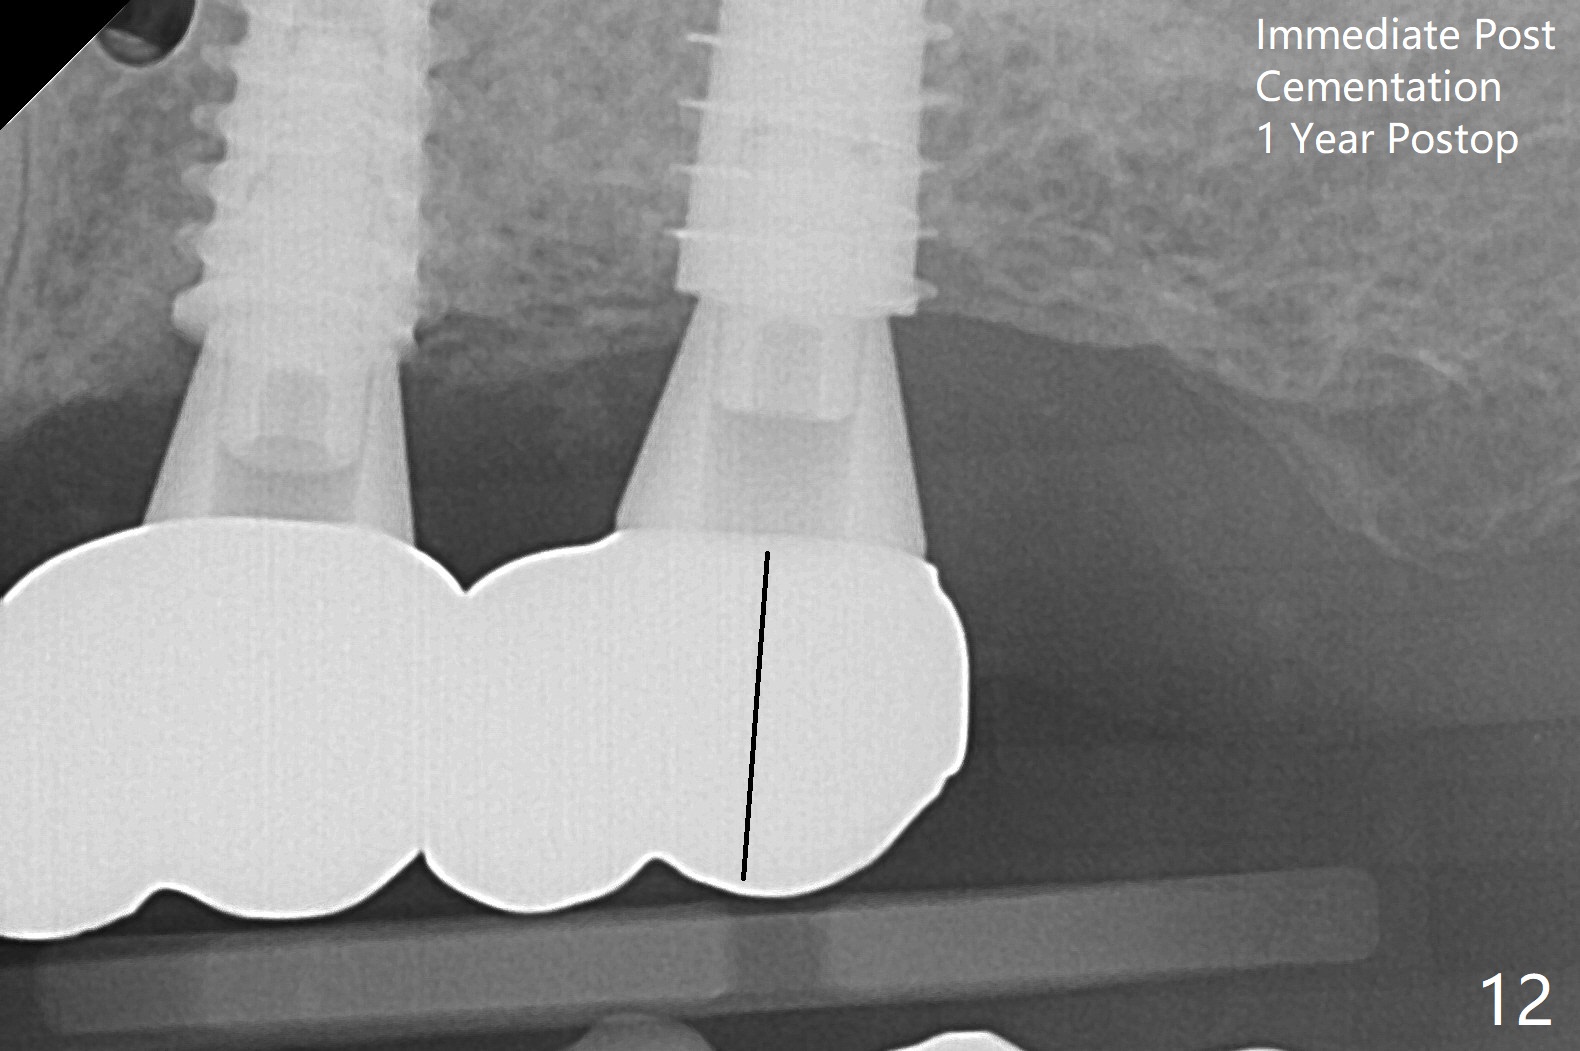

After finishing osteotomy with IS guide and Tatum Tapered tap 5x14 mm for 11 mm (gingival level) free hand, a 5x11 mm Tatum implant is placed at #18 with >15 Ncm (Fig.1). Bone harvested from the site of #18 will be used for #15 sinus lift (Fig.2 * as well as allograft). By the similar fashion, osteotomy at #15 is finished according to IS drill sequence except underdrilling (4.0x7.3 mm drill with 2 O-rings). Following use of DIO Sinus Approach Kit and placement of 2 pieces of PRF membrane and mixture of autogenous and allograft for sinus lift, a 4.5x11 mm IBS dummy implant is placed (Fig.2). With more allograft for sinus lift, a 5x9 mm implant is inserted with >35 Ncm (Fig.3). At #18 the implant 2.5 months postop (Fig.4) seems ok with removal of the cover screw and placement of a healing cuff. The implant at #15 appears osteointegrated with sinus lift 2.5 months postop (Fig.5 *). Half month later, the implant at #18 is tender associated with unipost placement. The healing abutment returns. A pair abutment (5.5x4(4) mm; 25 Ncm) is placed at #15. When the patient returns 7 months postop, BWs are taken to confirm that the abutment at #15 is fully seated, whereas that at #14 is not (Fig.6). A healing abutment is then placed at #14. Osteointegration seems to occur at #18; there is no tenderness when a 4.5x3 mm abutment is placed (Fig.7). Provisional crowns are fabricated at #15 and 18 for progressive loading. When the patient returns 14 months postop, a 5x4(4) mm hex abutment is placed at #14 with apparent gap between the implant and abutment (Fig.8 (PA) open arrow). In fact the gap seems to be absent more coronally as shown by bitewings (Fig.9,10 <). All of the 3 crowns are cemented in situ (Fig.11, 12) although the one at #14 is removed with the abutment for removal of residual cement. When the latter is re-torqued, the abutment remains completely seated (Fig.12). However, the implants at #15 and 18 appear to be placed distally with free-end guides (black lines).